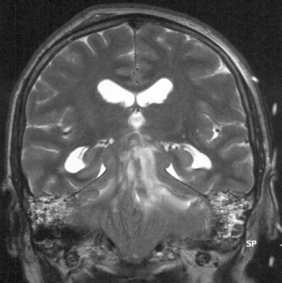

l’engagement rétro-mésencéphalique

c’est une figure particulière de dysfonctionnement de valve qui provoque la descente trans-tentorielle des hémisphères cérébraux sous pression en arrière du mésencéphale ; ceci donne une imagerie parfois déroutante (Cf. ci-dessous), mais qui traduit une HTIC sévère.